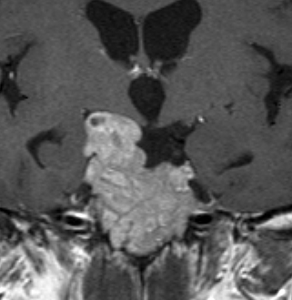

とても小さな腫瘍(微小腺腫) microadenoma

1cm以下の小さなものを微小腺腫といいます。ホルモンを異常に分泌する腫瘍は摘出する必要がありますが,そうでないものは治療の必要がありません。微小腺腫を数年観察しても増大する確率は10%くらいです。逆に,それ以上に大きなものだと,50%くらいの確率で増大します。

日本で汎用されているものでは最も解像力が高い3テスラMRIで撮影された,ガドリニウム増強像です。左側の画像では下垂体の大きさと形は正常に見えます。画像を調整すると,下垂体の内部,右端(黄色の矢印の先)に6mmくらいの小さな腺腫がみつかりました。MRIの性能がよくなったことによって数mmの小さなものも診断できるようになりました。